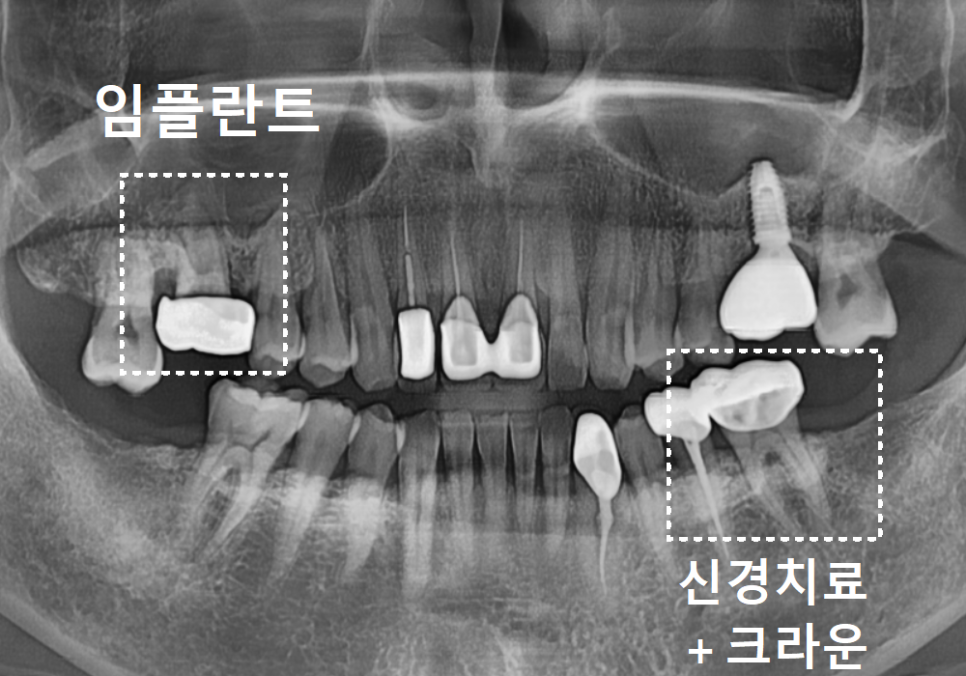

첫 번째 사례, 구멍 난 금니를 가지고 오신 환자분

상일역 치과, 오래된 금니 빠짐

처음 환자분이 오셨을 때는

오른쪽 위 어금니 금니가

빠져서 내원하셨는데요,

240812

가져오신 금니를 받아들고 살펴보니

세월의 흔적이 역력하더군요.

오랜 시간 씹는 힘을 견디느라

금니 표면이 닳아서,

구멍이 '뻥' 뚫려 있는 상태였습니다.

240812 상일역 치과, 오래된 금니 빠짐

입안을 들여다보니

상황은 생각보다 심각했습니다.

금니에 생긴 그 작은 구멍 틈새로

음식물 찌꺼기가 야금야금 들어가면서,

보철물 안쪽의 치아가

아주 심하게 삭아버린 상태였죠.

설상가상으로 뿌리 끝에는

거뭇한 염증 주머니까지 잡혀 있었죠.

결국 환자분의 고생을 줄이고

확실한 예후를 위해,

아쉽지만

발치 후 임플란트를 진행하게 되었습니다.

염증으로 녹아내린 잇몸뼈를

단단하게 보강하는

뼈이식을 하고,

임플란트를 식립했습니다.